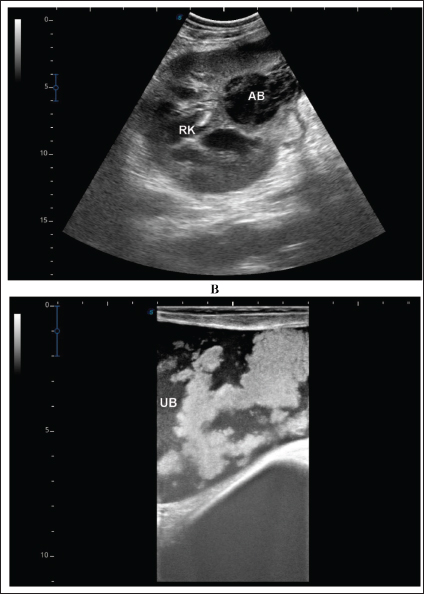

Single or multiple renal abscesses were visualized sonographically compressing the renal parenchyma. Three abscesses measuring 5.2–15.0 cm were scanned in 2 camels (11.8%); one affected the left and the other affected the right kidneys. In addition, 2 abscesses were imaged in 2 camels; both affected the left kidney. However, single abscesses measuring 3.6–14.0 cm in length were recorded in the remaining 13 camels; 9 in the right and 4 in the left kidneys. The contents of the abscesses were hyperechogenic in 8 cases (47.1%), hypoechoic in 4 (23.5%), isoechoic with hyperechoic foci in 3 cases (17.6%), and heterogenous in 2 (11.8%). In 4 of the diseased camels (23.5%), hyperechoic urine together with echogenic deposits was found within the urinary bladder (Fig. 6 and Fig. 10). Overall, unilateral lesions were found in the right kidneys only in 9 cases (52.9%) and in the left kidneys only in 6 cases (35.3%), while bilateral affection of both kidneys was found in 2 cases (11.7%). In the control camels, both kidneys appeared subjectively normal with no detectable lesions.

A detailed description of the renal abscesses is presented in Figures 410. Figure 4 shows sonographic findings in camel number 1 with abscessation of the right and left kidneys. A large abscess measuring 12.5 × 11.6 cm with hypoechoic contents and a thick capsule was detected. A second abscess in the same camel was imaged compressing the parenchyma of the right kidney and measuring 7.2 × 7.9 cm with echogenic contents and a thick capsule. Figure 5 shows ultrasonographic results in camel numbers 2 and 4 with right kidney abscesses. The lesions in camel number 2 appeared markedly large, compressing the renal parenchyma, with echogenic contents and a thickened capsule. The lesion in camel number 4 appeared to compress the renal parenchyma of the right kidney, measuring 6.7 × 8.2 cm with echogenic contents and a thick capsule. In addition, Figure 6. clarifies sonographic findings in camel number 6, where the abscess appeared within the right kidney. The contents were heterogeneous, but the capsule could not be imaged. The urinary bladder in the same animal was imaged with echogenic deposits that appeared highly echogenic compared with the echogenic urine.

Fig. 6. Ultrasonographic findings in camel number 6. The lesion in image A appeared within the right kidney (RK). The contents are heterogenous, and the capsule is not evident. Image B shows the urinary bladder (UB) in the same animal with echogenic deposits that appeared highly echogenic compared with the echogenic urine.